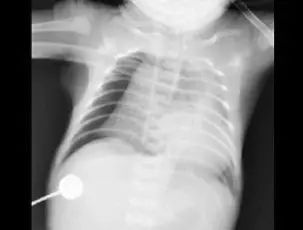

近日,成都1岁多的女孩豆豆(化名)经四川省妇幼保健院急诊科绿色通道快速进入重症医学科抢救。一天前还是活蹦乱跳的孩子,突然被送进重症监护室,而更令所有人大吃一惊的是,胸片显示,孩子的左肺竟然“不见了”?!

7月29日,原本身体很好的豆豆,不知为什么总会连续咳嗽,甚至嗓子都出现了沙哑,还突然出现哮喘,气促、呼吸困难等症状。在医院做完检查后,而胸片的结果却让在场所有人震惊:孩子的左肺竟然“不见了”?!

资料图

肺从片子上消失,医学上称为“白肺”。正常的肺部有空气进入,在 CT片上是呈影的。“白肺”,即肺部显影呈一大片的白色状,起因一般是重症肺炎或者大量的胸腔积液。但是豆豆并没有肺部疾病史,究竟是什么原因呢?